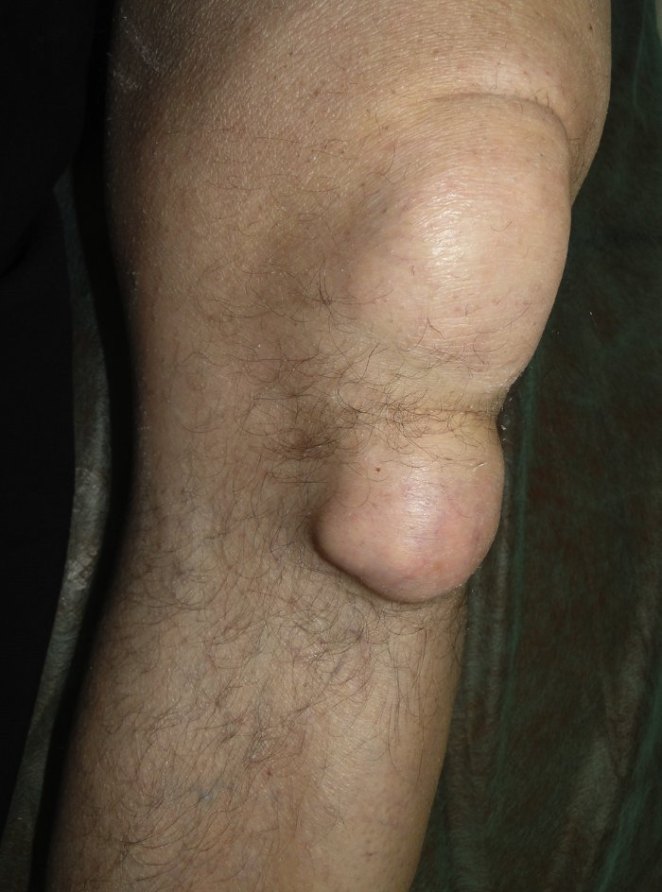

Proyección Anteroposterior de rodilla que muestra: 1) calcificación en cuña del menisco 2) calcificación en cuña siguiendo en paralelo al cóndilo femoral.

El espacio articular se encuantra conservado, nótese las radiodensidades con distribución punteada o lineal.